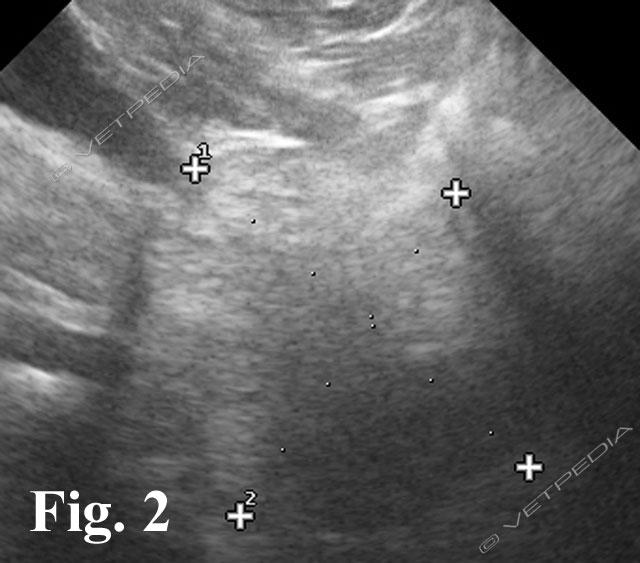

L’esame radiografico di norma si può eseguire senza sedazione; si può eventualmente eseguire una breve anestesia gassosa con induzione diretta. Viste le dimensioni della cavia, conviene eseguire di routine le proiezioni laterale e ventrodorsale di tutto il corpo, a meno che l’animale non sia gravemente debilitato e manovre stressanti poss...